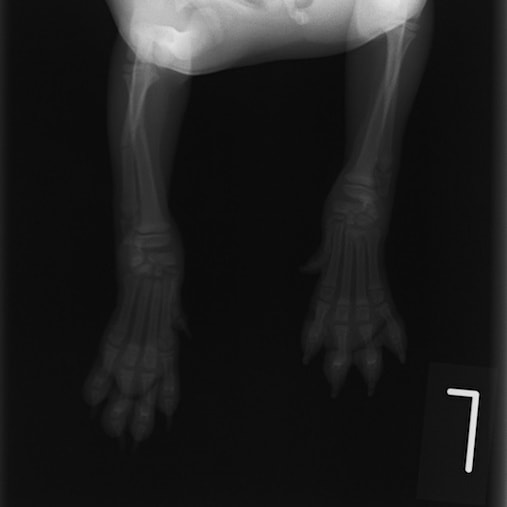

トイプードル 右遠位橈尺骨短斜骨折のALPSによる内固定